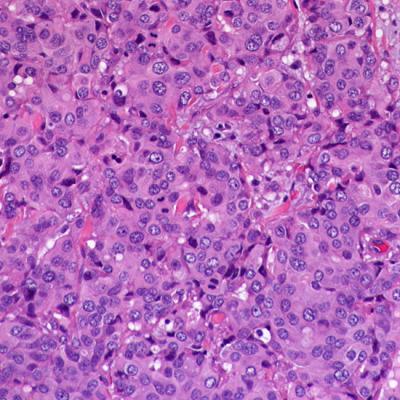

Invasive lobular carcinoma, which is characterized by a unique growth pattern in breast tissue that fails to form a lump, has distinct genetic markers that indicate there may be benefits from drug therapies beyond those typically prescribed for the more common invasive ductal carcinoma. The results will be published in the March 1 issue of the journal Cancer Research .

Patients with invasive lobular carcinoma are typically treated through surgical removal of the cancer, followed by chemotherapy or hormone therapy or both, usually with the estrogen-mimicking drug tamoxifen or estrogen-lowering aromatase inhibitors, the same as patients with invasive ductal carcinoma.